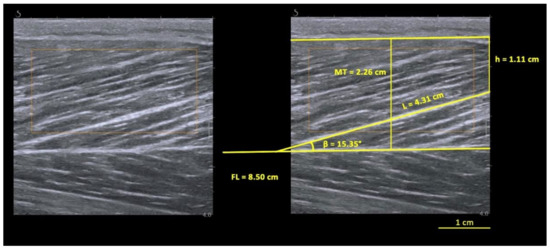

Prior selection of the sonograms matching the criteria explained below was performed for each video recorded. All sonograms were digitized using ImageJ software (NIH, 1.47v, Bethesda, MD, USA), and FL, PA and MT were determined from each sonogram. The researcher was blinded to the outcome during the digitization process. As only part of fascicle could be visualized during static-image assessments, the linear extrapolation method was used to estimate the non-visible portion of the fascicle (15) using the following Equation (1):

FL = L + (h/sinβ)

where L is the observable fascicle length from the mid-muscle aponeurosis to the most visible endpoint, h is the perpendicular distance between the superficial aponeurosis and the fascicle’s visible distal end-point and β is the angle between the fascicle (drawn linearly to the most distal point) and the superficial aponeurosis, as in Figure 1. The MT was measured as the distance between the superficial and the mid-muscle aponeurosis measured at the ROI site. For each condition, two videos were recorded, and a frame was selected from each video. This was conducted in pre- and post-task instants (totaling 8 images for each limb). Three fascicles were selected in each image, meeting the criterion that a reasonable portion of the fascicle (~25% or more of the total estimated length) must have been visible within the ultrasound transducer’s field of view to be included in the present study [31].

Figure 1. Biceps femoris long head (BFlh) architecture, measured at pre-task active condition. L, observable fascicle length; h, height; β, pennation angle; MT, muscle thickness; FL, fascicle length.